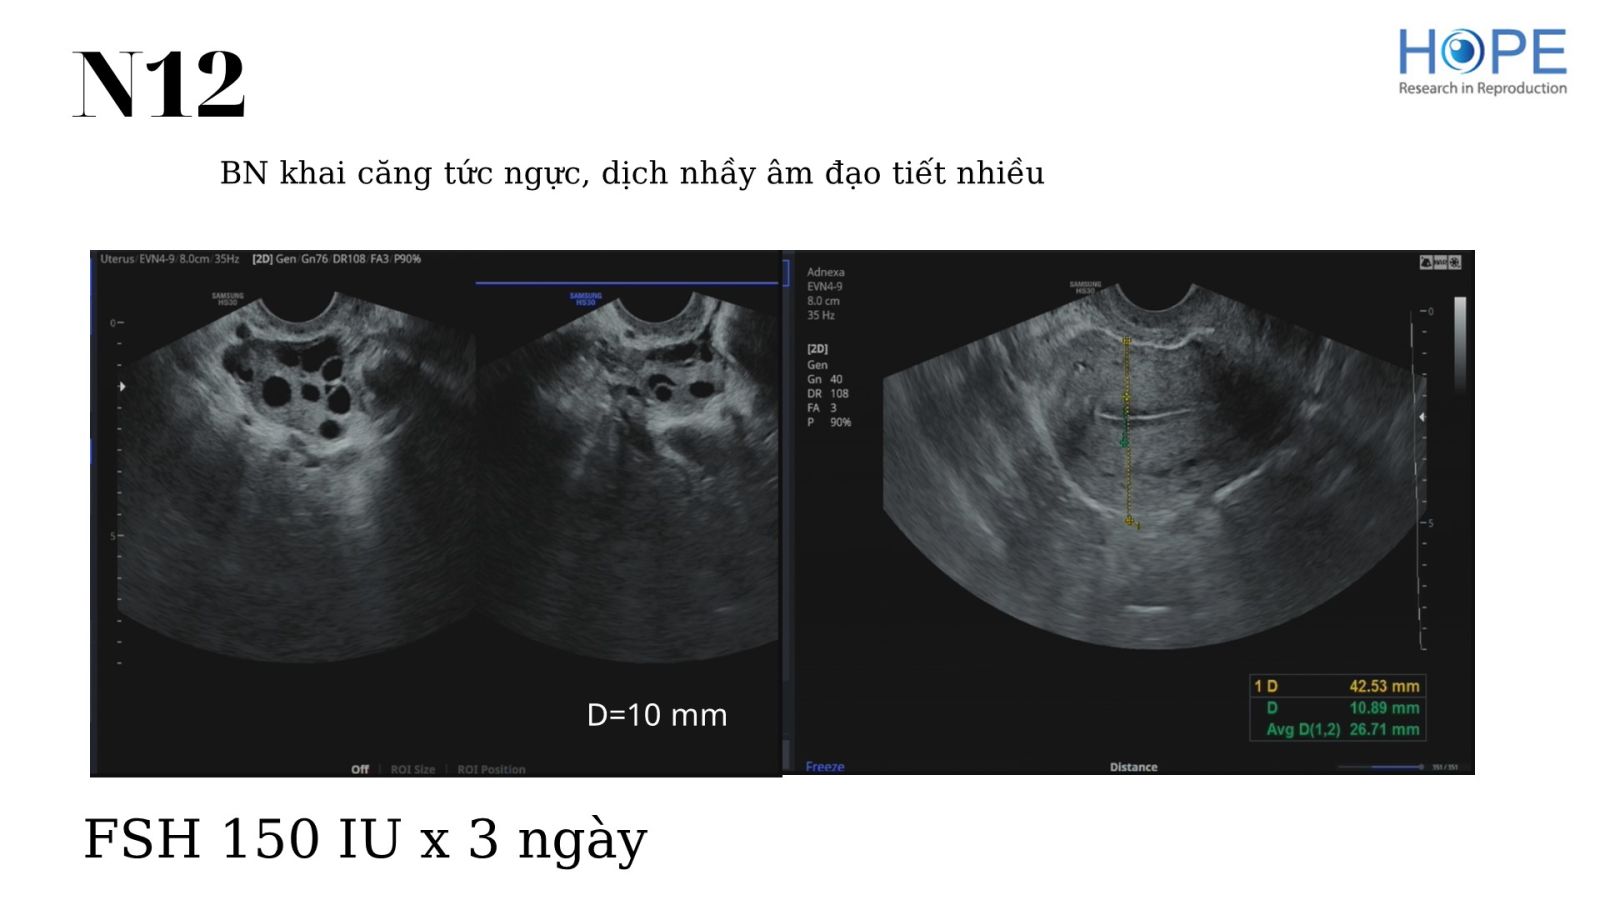

Các phác đồ kích thích buồng trứng nhẹ để IUI –  cách theo dõi kích thích buồng trứng

BS Lê Thị Hà Xuyên - IVFMD Phú Nhuận